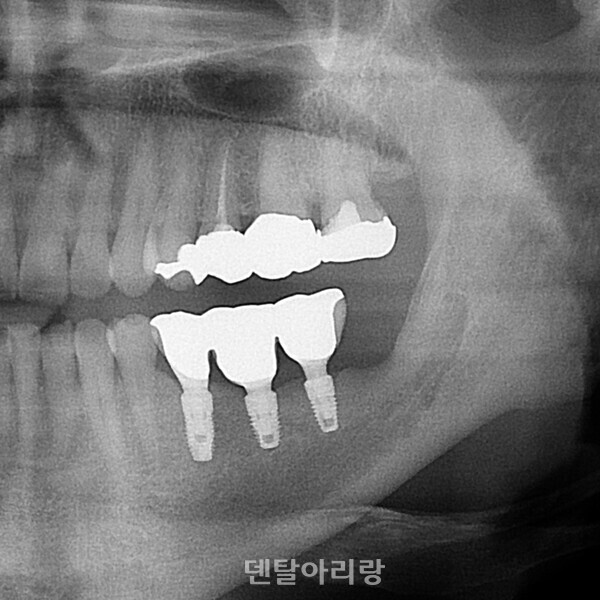

상악동 점막을 골점막(mucoperiosteum)이라 불리기도 하는데 조직학적으로 상악골과 하악골의 골막과는 다르고 상악동점막과 주변골사이에 골모 세포가 없기 때문에 아직 논란의 여지가 있다. 다만, 최근 여러 연구를 통해서 상악동 점막에 의한 골유도능력이 관찰되어 보고되기도 하였다. 실험을 통해 상악동 점막의 거상하여 골이식재 없이 거상 부위에 혈액과 임플란트만 식립하고 경과 후 현미경으로 분석한 결과, 임플란트 주변으로 신생골이 형성된 것을 관찰할 수 있었다(Clinical Implant Dentistry and Related Research, Volume 8, Number 1, 2006)<그림 17, 18>.

△그림 17. 상악동 점막 거상 후, 혈액이식 및 임플란트 식립

△그림 18. 상악동 점막에 의한 임플란트 주변 신생골 형성0

앞으로도 상악동 점막에 대한 연구가 더 필요하나, 확실한 것은 건강하고 손상되지 않은 상악동 점막은 상악동 골이식술 예후에 매우 긍정적인 영향을 미친다는 것이다.